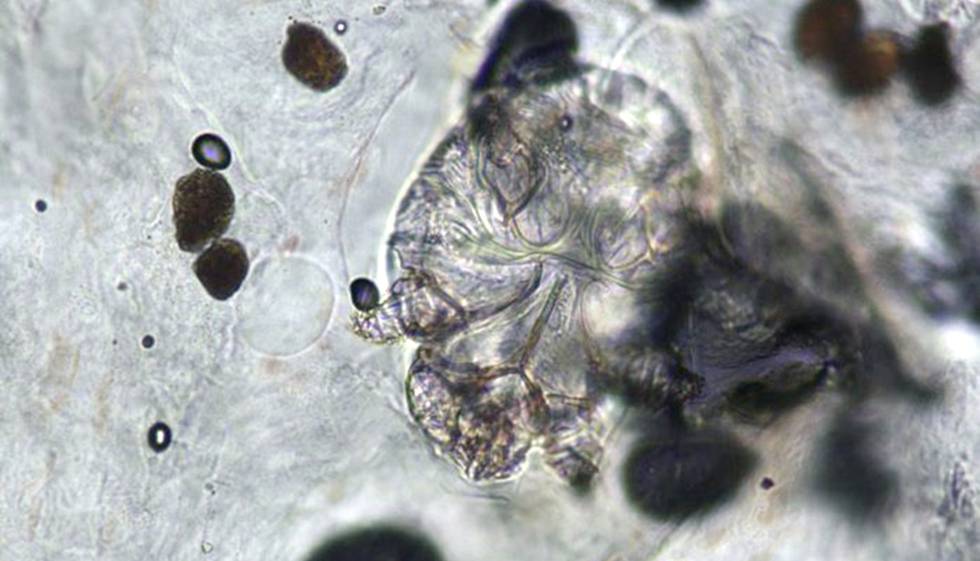

Imagen microscópica del ácaro que provoca la sarna.Hospital del Mar

La sarna, también conocida como escabiosis, está causada por el ácaro Sarcoptes scabiei, que produce intensos picores al moverse por la epidermis excavando túneles. Es bastante contagiosa entre personas cercanas, ya sea por el contacto directo piel con piel o por compartir espacios como la cama, un sofá… Es un proceso clínico considerado leve, pero que tiene un notable impacto en la vida del paciente porque, además de las molestias, la inflamación que produce y el rascarse muy a menudo acaba en unos vistosos eccemas que llegan a requerir tratamiento con corticoides e incluso antibióticos si se produce una infección por alguna bacteria oportunista.